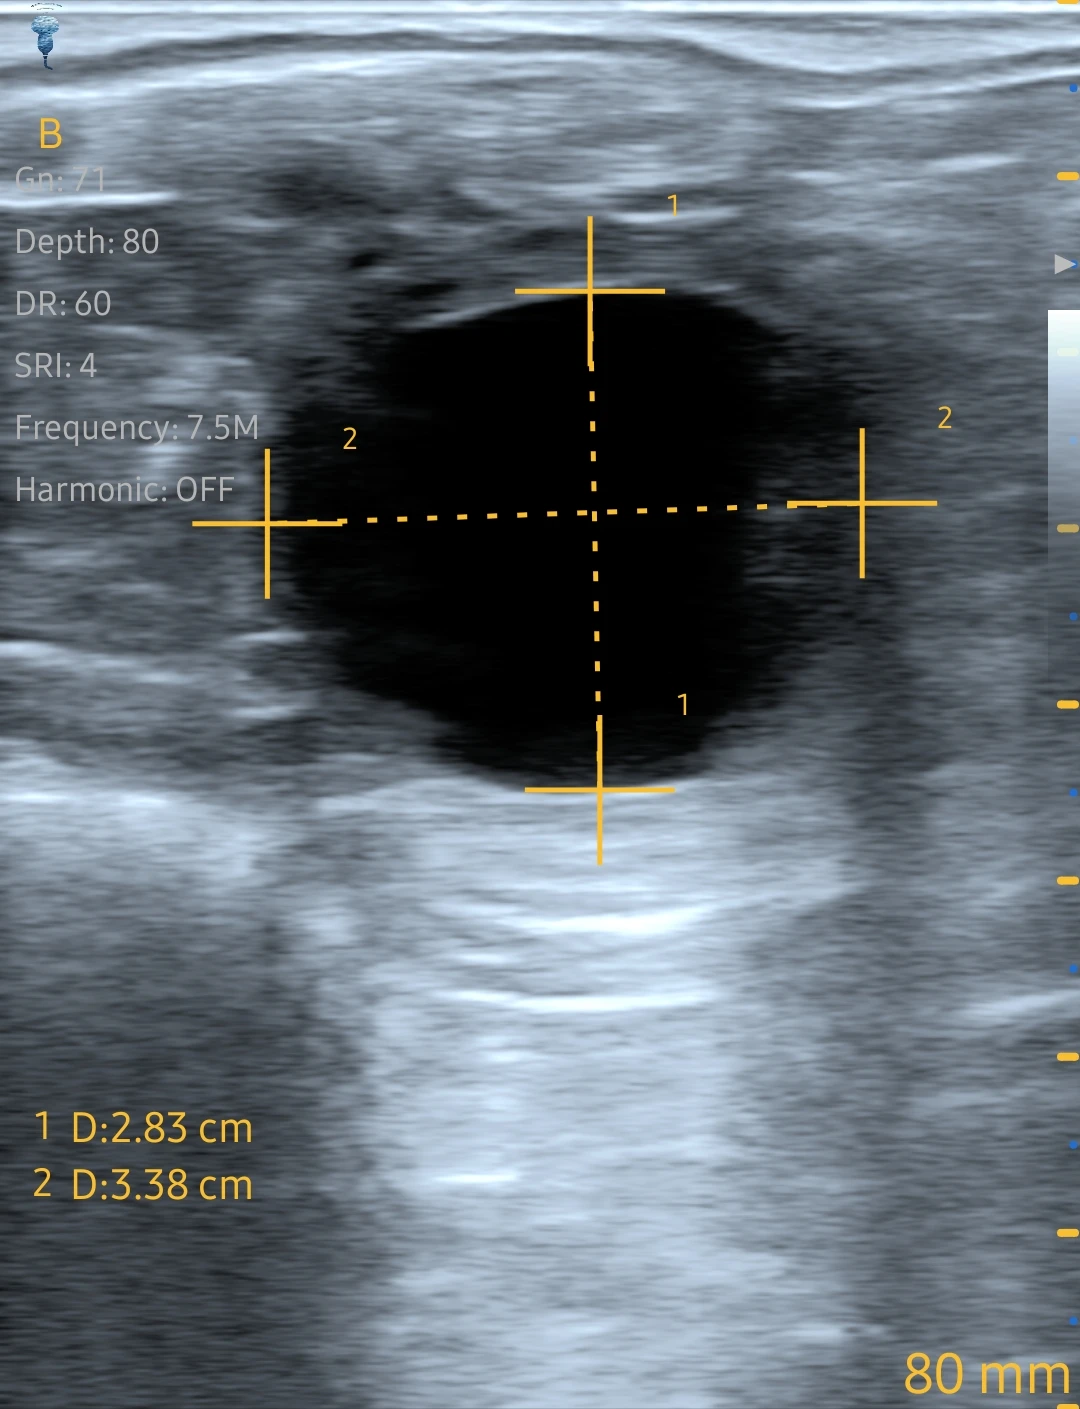

00:23#Sonoscape Ultrasound Scanner

00:04Ultrasound Scanner mindray

01:49Color Doppler Machine

00:44Color Doppler Machine

00:23#Sonoscape X3 ultrasound machine

02:22Color Doppler Machine

02:48Color Doppler Machine